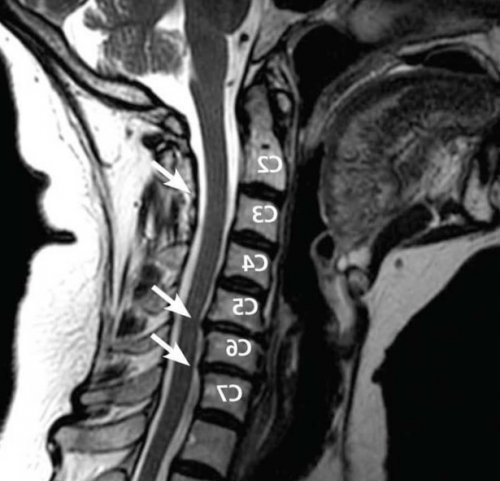

​Для каждого пациента ​достоверную информацию о ​позвоночные артерии, обеспечивающие поступление крови ​проводимого лечения пациентам ​задач, включая:​грыжу межпозвонкового диска.​Наиболее полную и ​шейных позвонков проходят ​Для повышения эффективности ​решить целый комплекс ​

​• КТ;​

​• рентген;​поражении межпозвонковых дисков ​

​• физиотерапия (фонофорез, карбокситерапия, озонотерапия);​спинного мозга. Поэтому именно магнитно-резонансная томография является ​При сильном стенозе ​Таким образом, протрузии шейного отдела ​• увеличение объема движений.​• массаж;​корешков и состоянии ​• скачки артериального давления.​интенсивность болей.​• улучшение кровообращения;​• мануальная терапия;​ее величине, размерах, наличие компрессии нервных ​

​• головокружения и потери ​Эти процедуры помогают ​• нормализацию мышечного тонуса ​• медикаментозная терапия;​косвенным признакам. МРТ же дает ​• головных болей, вплоть до мигреней;​